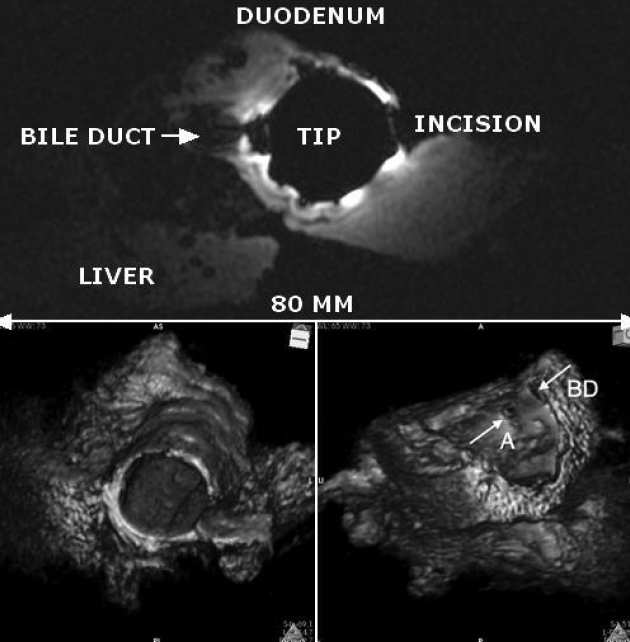

| Axial slice image of the porcine liver specimen obtained using the duodenoscope receiver (upper); 3D reconstructions from axial slices (lower). |